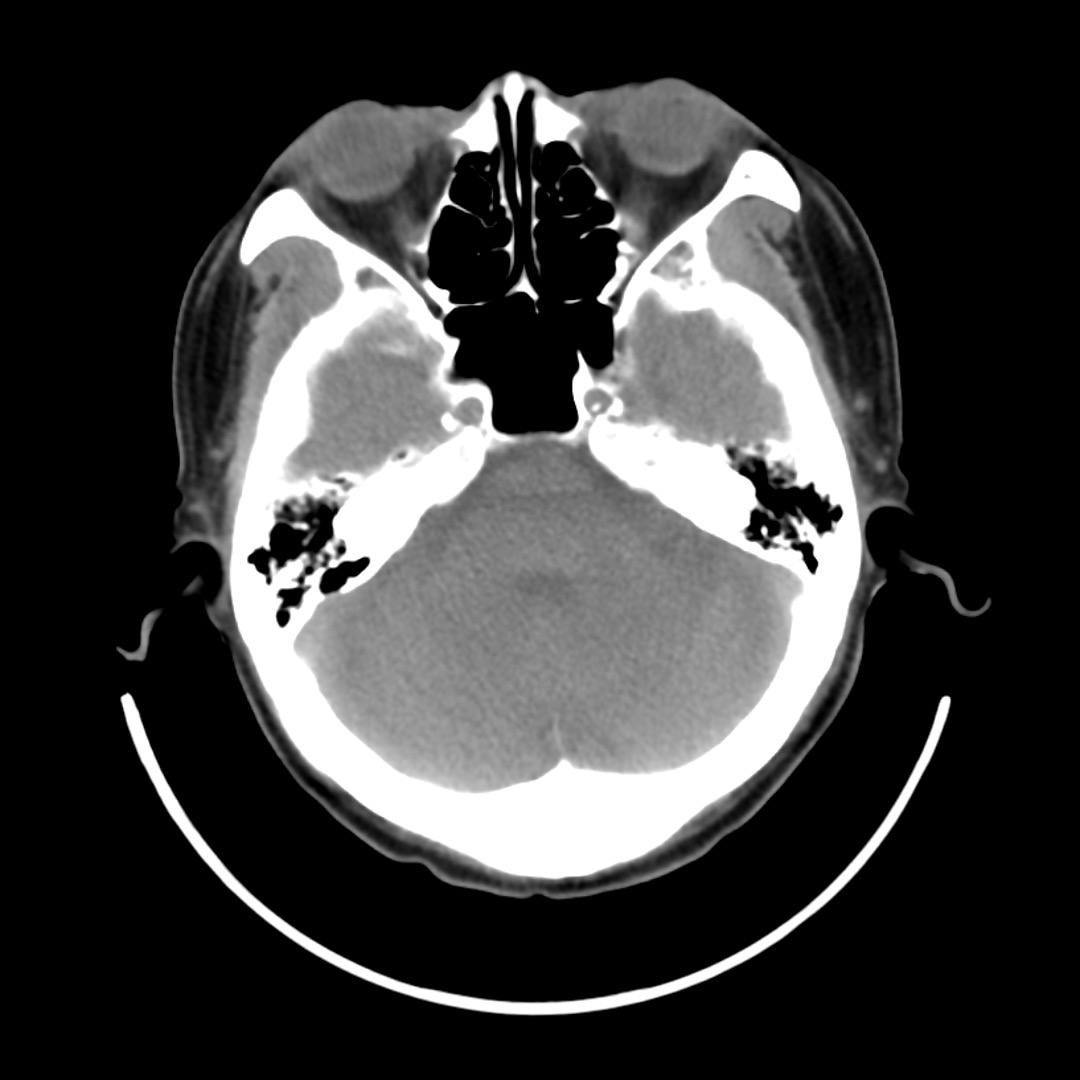

のどに違和感がある90歳代男性

施設入所中の90歳代男性.前日に家族と外出し,夕食をとった.本日,薬を飲む際にのどの違和感と軽度の痛みを自覚.その後も症状が持続しているため受診.

意識清明,体温36.7℃,心拍数61回/分,血圧142/80 mmHg,SpO

99%(室内気).唾液を飲み込む際に咽頭あたりに違和感の訴えあり.他覚的な異常所見なし.

Q1:頸部単純CT(図1)で認められる画像所見・診断は?

図1 頸部単純CT横断像